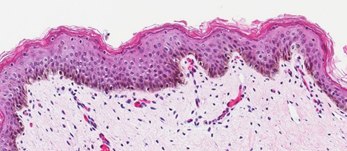

Neonatal Skin Tissue (B)

Figure 2. Organotypic skin models have stratified epithelial morphology comparable to neonatal skin tissue. H&E staining of in vitro skin culture and ex vivo skin sections containing both dermal and epidermal stratified layers (A, B). Filaggrin staining identifies cornified keratinocyte layers (brown) (C, D).